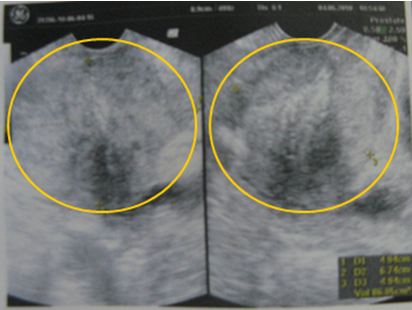

Bệnh nhân đã dược chụp PET/CT: Tuyến tiền liệt to, kích thước: 6 x 4,9 x 5,1 cm, nhu mô không đồng nhất, có nhiều nốt vôi hoá, thuỳ phải to hơn thuỳ trái, tăng hấp thu FDG không đồng đều, max SUV=4,98.

Hình 2: Hình ảnh PET/CT: tuyến tiền liệt (trong vòng tròn màu xanh) tăng hấp thu FDG không đồng đều, max SUV=4,98

Giá trị của PET/CT trong ung thư nói chung và ung thư tuyến tiền liệt nói riêng là chỉ trong một lần ghi hình (khoảng 30-45 phút, tùy bệnh); các bác sỹ có thể thu được cả hình ảnh CT bao gồm các thông tin chính xác về giải phẫu, vị trí cùng với hình ảnh chuyển hóa của PET cho ta thấy những thay đổi ở mức độ phân tử, tế bào ở giai đoạn rất sớm. Hệ thống máy máy PET/CT ở Trung tâm YHHN&UB bệnh viện Bạch Mai được trang bị đồng bộ, thống nhất nên hình ảnh PET/CT không chỉ sử dụng để chẩn đoán mà còn được sử dụng trực tiếp để lập kế hoạch xạ trị, định hướng cho vị trí sinh thiết.